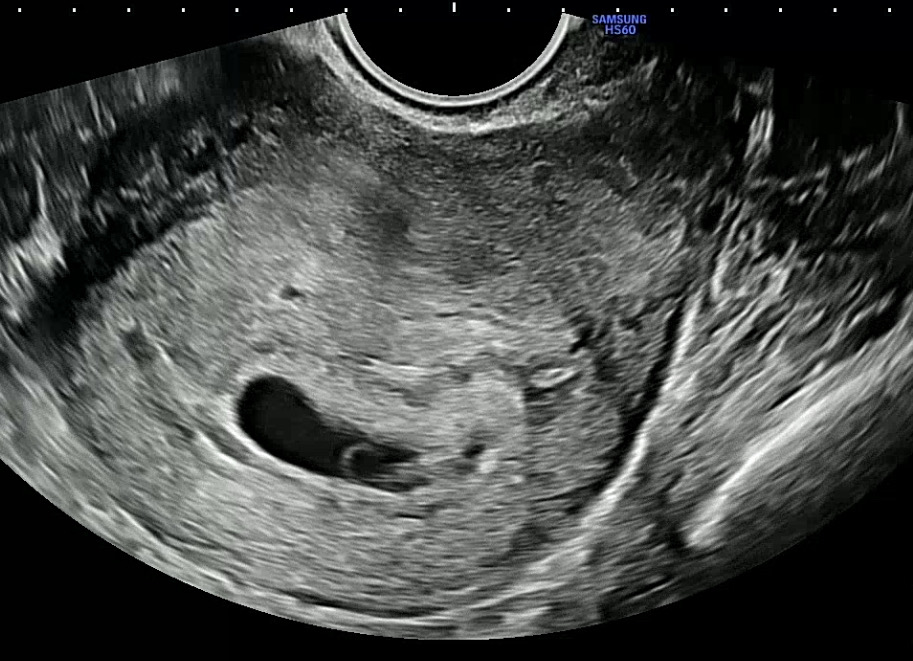

5주6일

날짜로는 6주인데 쪼금 늦배란인것같다고 하시던데 심소를 듣긴했는데 너무 작게 들리고 난황도 엄청 희미하게 보여서 걱정이에요 저처럼 희미하게 보이는 난황 보신분 있으시나요 애기보이는 각도에서는 난황 보이지도 않아요...

그런거 맞겠죠? ㅜㅜ 걱정에 괜히 초음파 영상만 계속 돌려보고있어요 ㅜㅜ